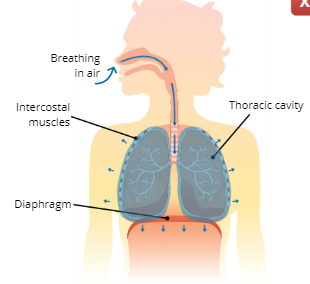

What are the 3 major respiratory muscles?

Diaphragm, External Intercostal Muscles, and Internal Intercostal Muscles

Diaphragm

a dome-shaped muscle below the lungs that separate the thoracic and abdominal cavity

External Intercostal Muscles

pull ribs upwards and outwards

Internal Intercostal Muscles

pull ribs downwards and inwards

Inhalation (inspiration)

Explain the Process of Inhalation (Inspiration)

The intercostal muscles and diaphragm contract, this causes the thoracic cavity to expand which increases lung volume, the increase in lung volume creates a suction that pulls air into the lungs